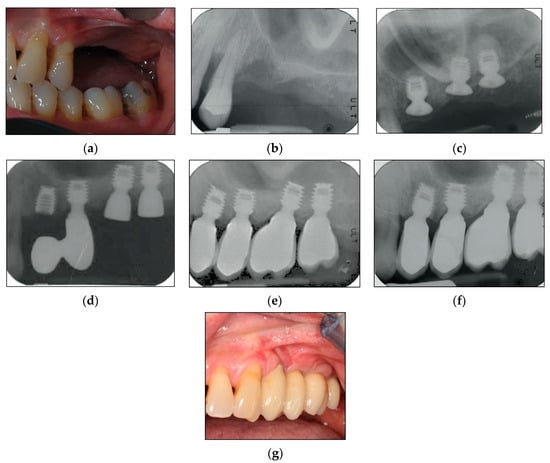

2.2. Surgical Protocol

2.3. Prosthetic Protocol and Follow-Up Evaluation